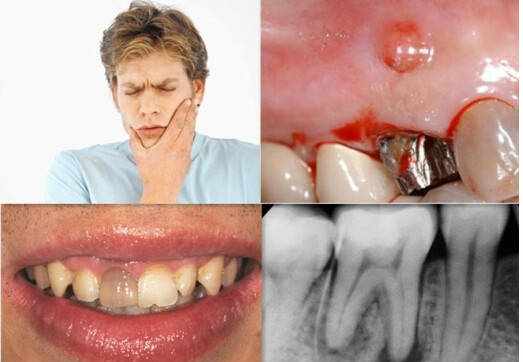

龋齿是口腔最常见的疾病之一,俗称蛀牙,更加通俗的描述就是在牙齿上出现了小洞、大洞,甚至大面积的牙体缺损。

如果没有引起足够重视会引起多种令人头痛的后续问题,所谓小洞不补,大洞吃苦。

口腔中的细菌可以在牙齿表面堆积形成牙菌斑生物膜,其中的致病菌分解唾液中的糖产酸,酸会破坏牙齿,形成龋洞。

此时龋洞需要进行充填,否则会继续被侵蚀,导致牙神经损伤甚至牙神经死亡,感染或发生脓肿。因此,牙神经损伤需要进行根管治疗。